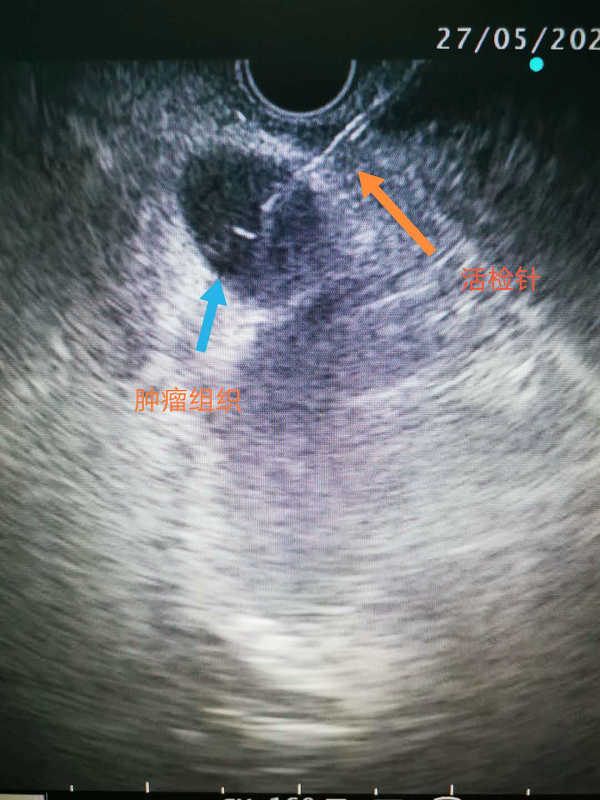

EUS-FNA是在超声内镜实时引导下,使用专用穿刺针,对消化道管壁及周围病灶进行穿刺抽吸以获取组织细胞学诊断的一种技术。

经过精确超声内镜定位后,刘医生准确穿刺到病变部位取到病理组织,至此医院首例EUS-FNA圆满成功。术后病理结果显示为淋巴瘤,在明确病因后,患者也准备开始下一步的治疗。